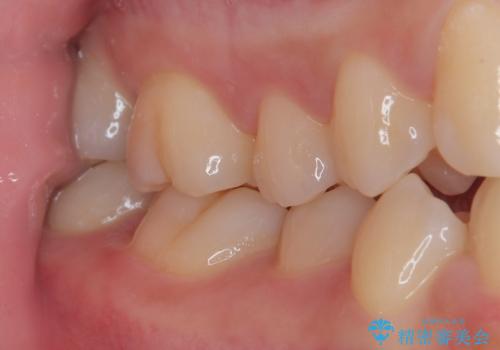

ゴールドインレー(PGAインレー)はセラミックインレーと比べ、歯の切削量が少なく、適合性が著しくいいことが特徴です。上顎の奥歯は見えないので機能面でゴールドインレー、ゴールドクラウンはおすすめです。

違和感がないと喜んでいただきました。